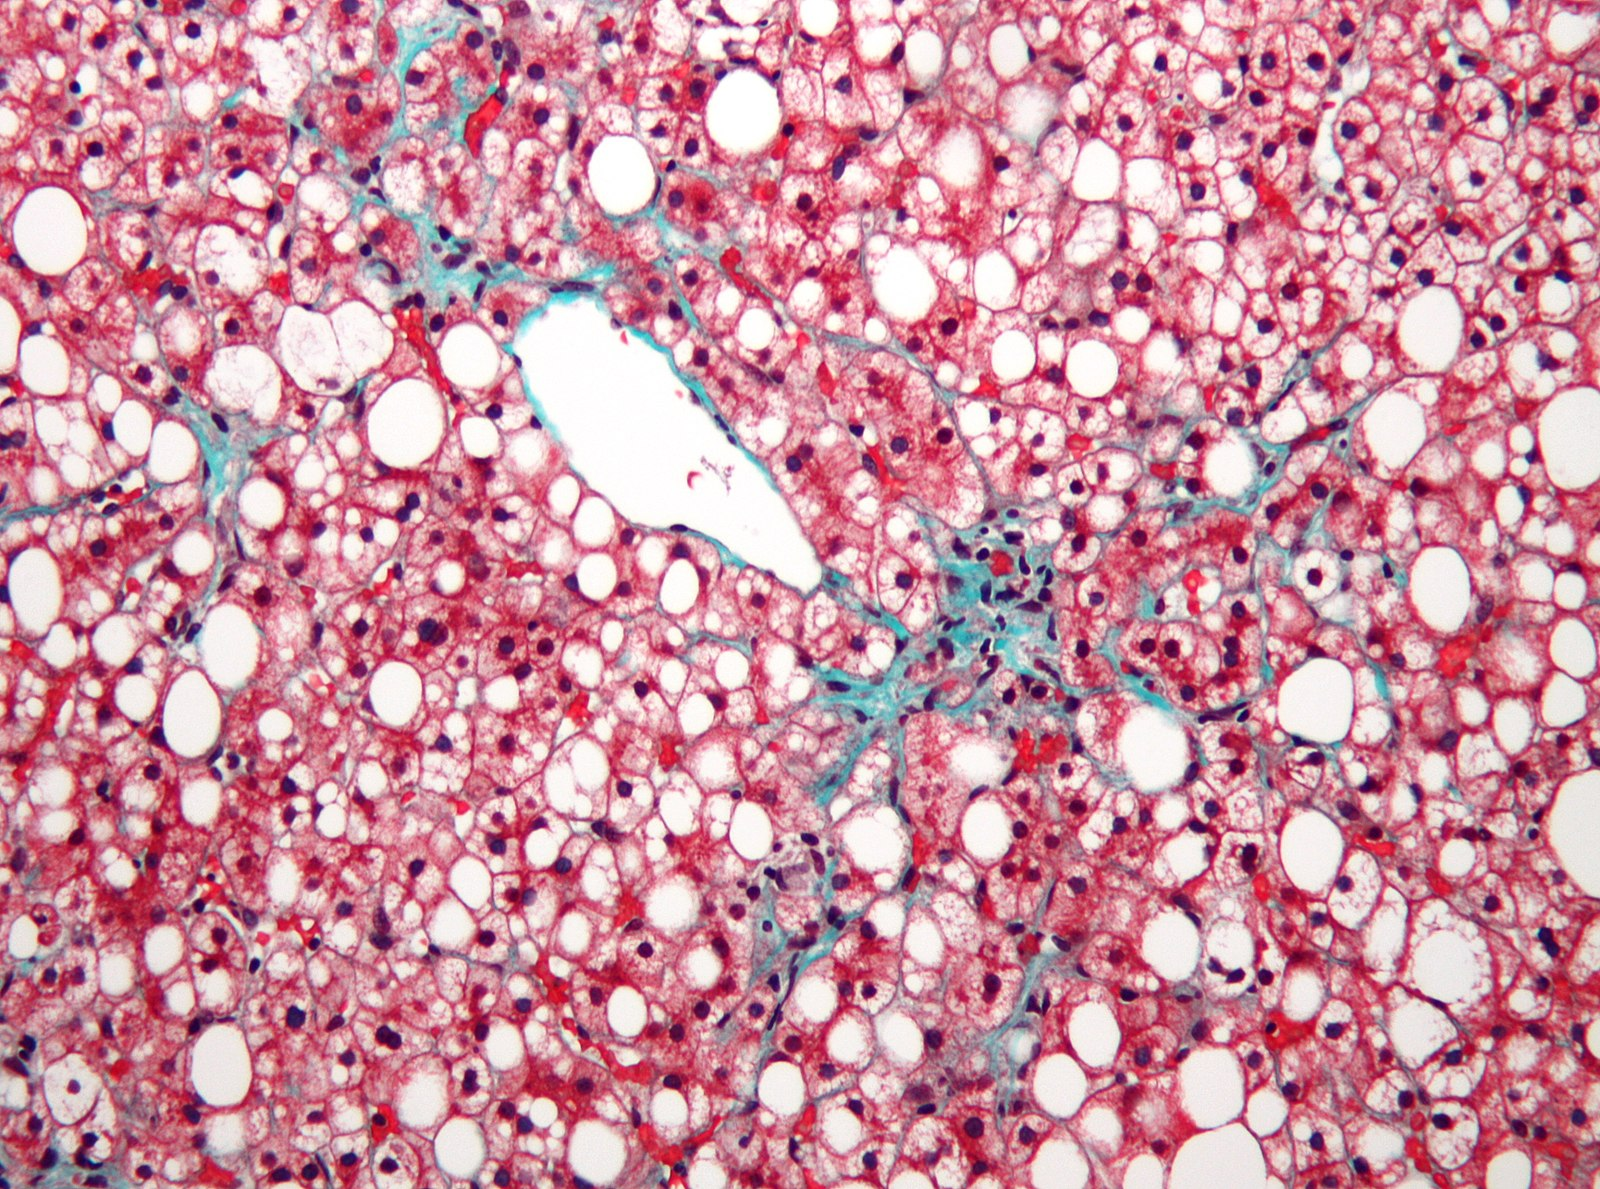

El hígado puede agrandarse ligeramente por la presencia de estas grasas, pero en este punto la enfermedad no da síntomas porque la función del hígado se mantiene. La única forma de ver que existe esteatosis es mediante pruebas diagnósticas en las que se observe que más de un 5 % del contenido del hígado son grasas, que se observan como esferas blancas dentro de las células:

Sección de hígado de un paciente con MASLD. Los depósitos de grasa aparecen como esferas blancas dentro de las células. Fuente